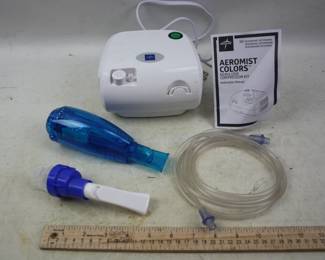

5145 - Medline Aeromist Nubulizer Breathing Therapy